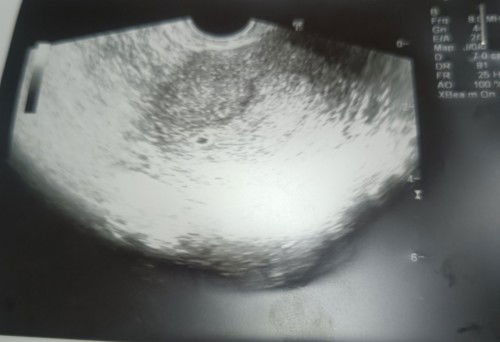

Ada yang pandai baca scan x? gambar ni dari TVS scan.. doctor ckp pregnant, buat bhcg pun dpt result pregnant (1200++).. tp pakar gh xdapat nak confirm berapa weeks sbb irregular period & kantung sekecil itu.. pakar suspect pregnant around 4weeks, tp x dpt bg confirmation lg.. suruh repeat next 2 weeks.. ada moms pengalaman lebih kurang sama? sy risau 😭 #pleasehelp #advicepls #firsttimemom #firstbaby #ingintahu #pregnancy